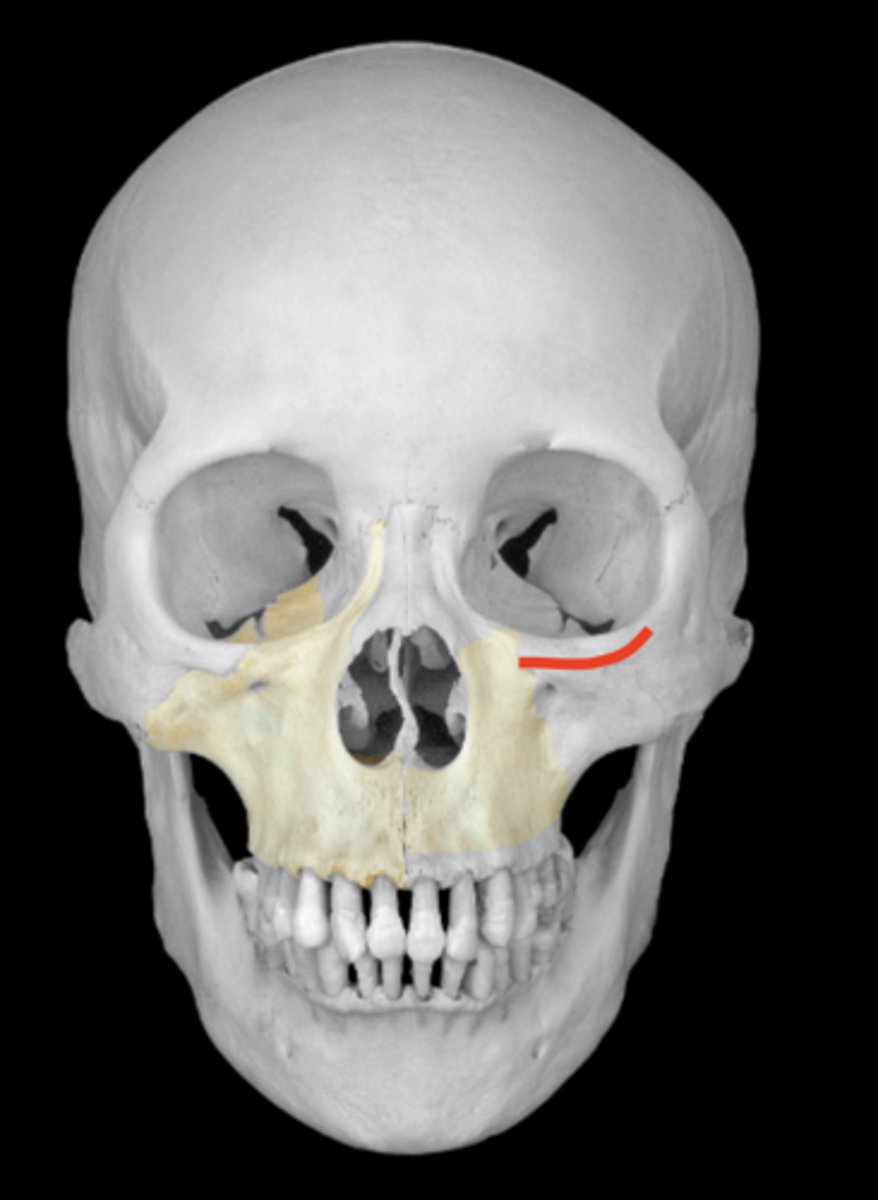

palatine processes of the hard palate of maxillae

median palatine suture of maxillae

transverse palatine suture of maxillae

orbital surface of the maxilla

infraorbital margin of the maxilla